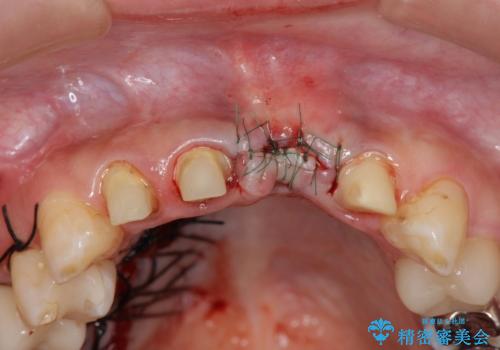

不良インプラントを除去し最終的にブリッジによる補綴で審美性の改善を行うこと、その準備として骨の造成・歯肉の移植による歯の欠損部顎堤のボリュームを維持・増大を計画します。

より審美的な改善を強く求められたため、インプラントを除去し可及的に欠損部顎堤を増大したのちブリッジによる審美改善を行いました。